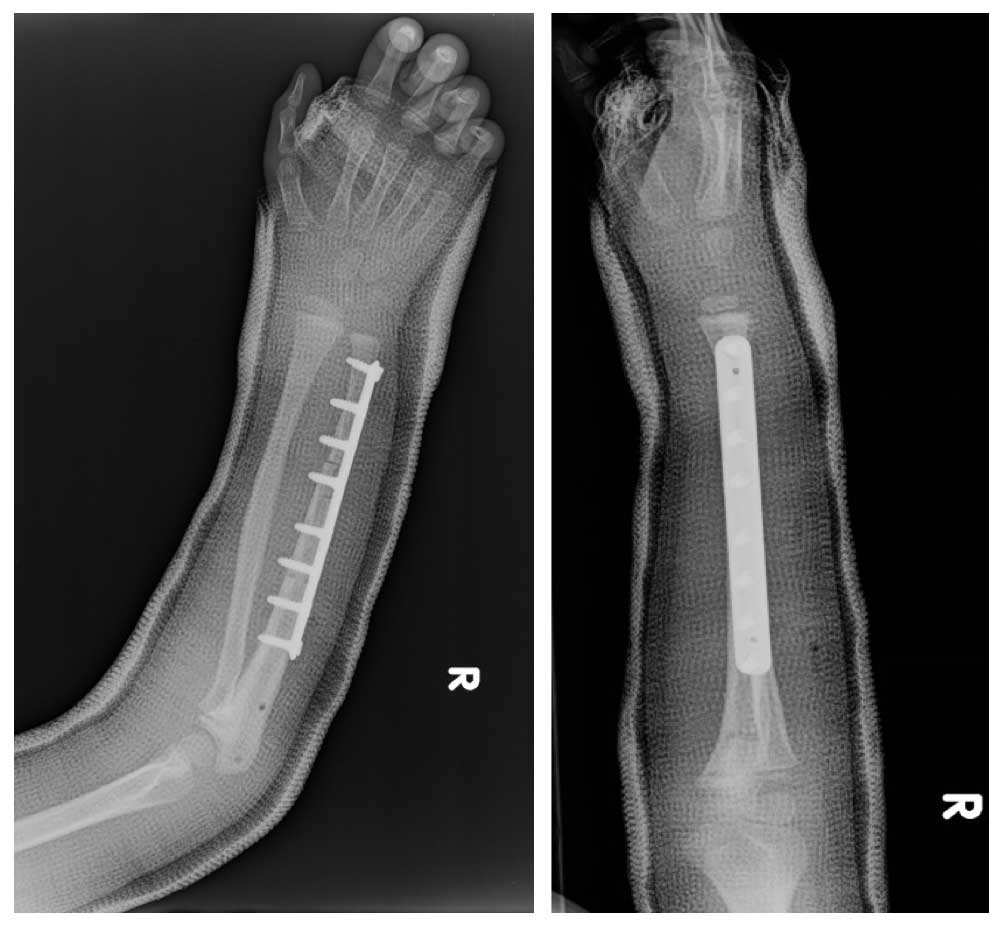

Ameliyat Sonrası: Röntgende geri kazanılan kemiğin plak ile fiksasyonu görülmekte.